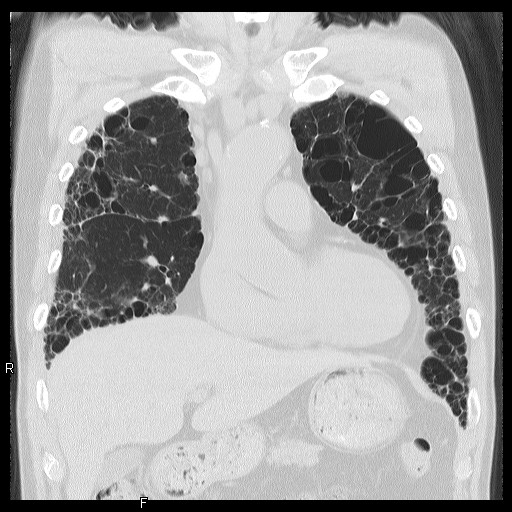

血管ドックの目的は、自覚症状がない段階で心臓や身体の血管、肺や肝臓などの臓器の病気を発見し、病気あるいは、その進行を未然に予防しようとすることです。CT検査は主に、動脈狭窄や動脈瘤などの血管性病変の発見、胸腹部臓器の悪性新生物などの腫瘍性病変の発見に有用です。

- 肺癌検診(CT)

肺がん

慢性間質性肺炎・肺気腫